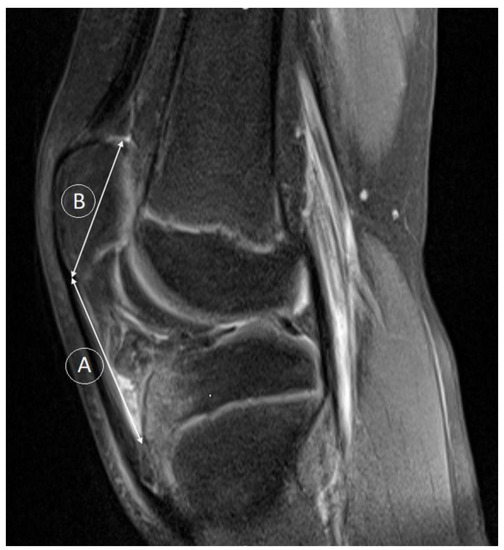

- Verhulst, F.V.; van Sambeeck, J.D.P.; Olthuis, G.S.; van der Ree, J.; Koeter, S. Patellar height measurements: Insall-Salvati ratio is most reliable method. Knee Surg. Sport. Traumatol. Arthrosc. 2020, 28, 869–875. [Google Scholar] [CrossRef] [PubMed]

- Kurowecki, D.; Shergill, R.; Cunningham, K.M.; Peterson, D.C.; Takrouri, H.S.R.; Habib, N.O.; Ainsworth, K.E. A comparison of sagittal MRI and lateral radiography in determining the Insall-Salvati ratio and diagnosing patella alta in the pediatric knee. Pediatr. Radiol. 2022, 52, 527–532. [Google Scholar] [CrossRef] [PubMed]

- Thévenin-Lemoine, C.; Ferrand, M.; Courvoisier, A.; Damsin, J.P.; Ducou le Pointe, H.; Vialle, R. Is the Caton-Deschamps index a valuable ratio to investigate patellar height in children? J. Bone Jt. Surg. 2011, 93, e35. [Google Scholar] [CrossRef] [PubMed]